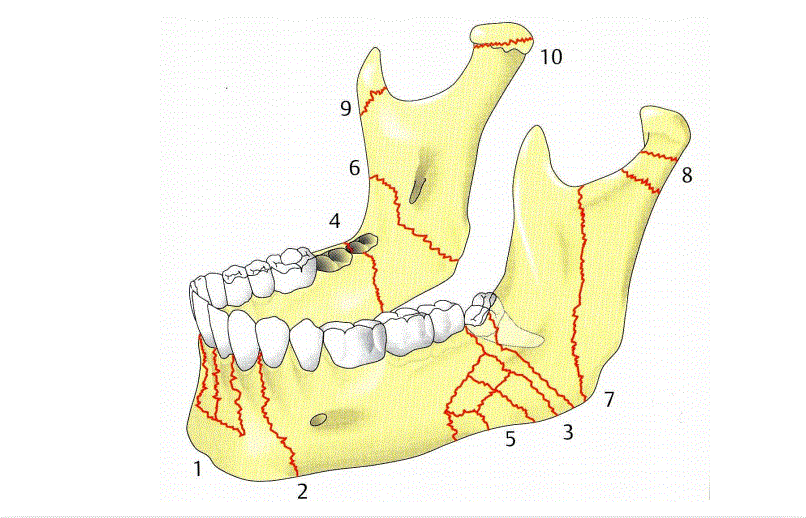

Le Fort 1-3 , grob Frakturverläufe erklären